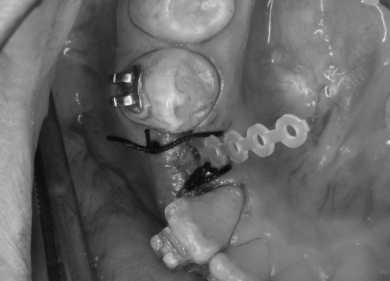

②両側の歯と骨の中に埋まっている永久歯にブラケットを装着し、ゴムの力で牽引していきます。

③ある程度の高さまで永久歯が萌出し、ブラケットがつけられるようになったらワイヤーをつなげ位置を調整する。